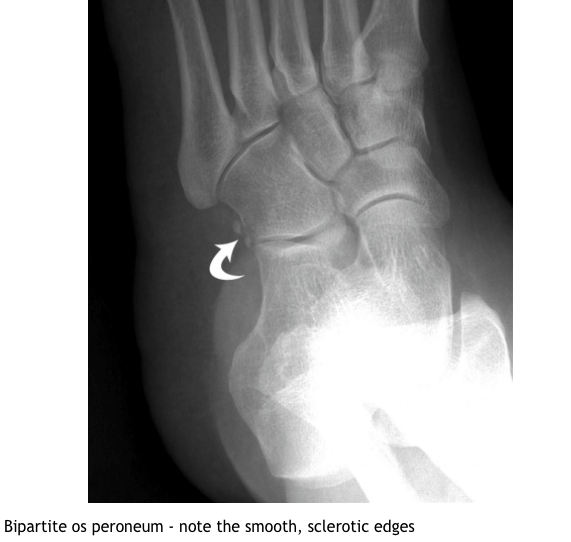

What investigations are useful in DDx of Os peroneum?

What is the DDX of Os peroneum?